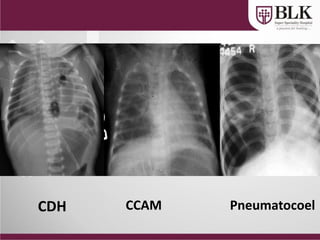

CDH CCAM Pneumatocoel

pneumothorax

CLE CLE